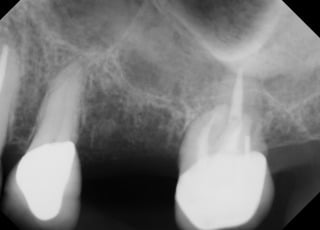

Erin

This patient had a implant place to replace a tooth which had been removed due to infection.